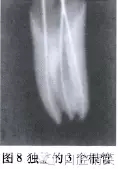

44冠方殘端可見3個(gè)根管口,與牙根相應(yīng)分別位于近頰、遠(yuǎn)頰及舌側(cè)(圖7)。3個(gè)根管口分別插入#15擴(kuò)大針可達(dá)相應(yīng)3個(gè)根尖,x線片示3個(gè)根管相互獨(dú)立(圖8)。